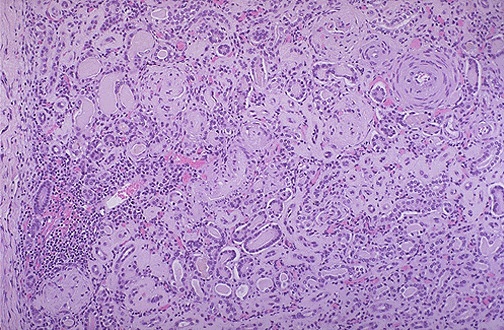

An abdominal CT shows markedly enlarged cystic kidneys bilaterally.